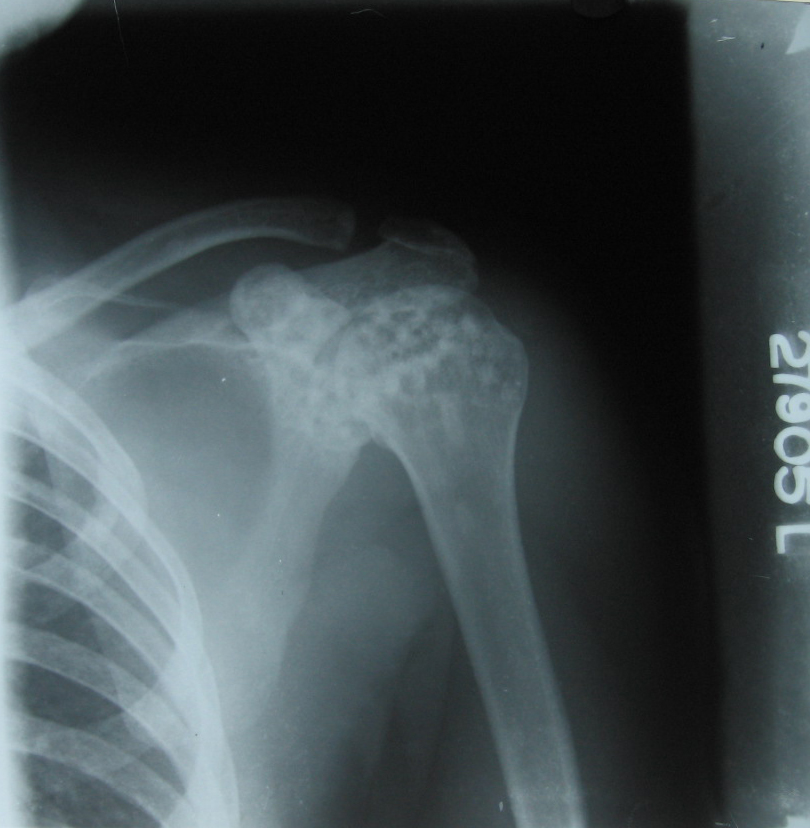

FIG 1osteopoikilosis shou